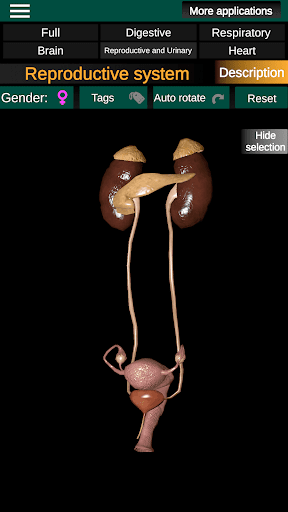

* Репродуктивна система, яка включає чоловічі та жіночі репродуктивні органи.

* Порівняйте чоловічі та жіночі органи.